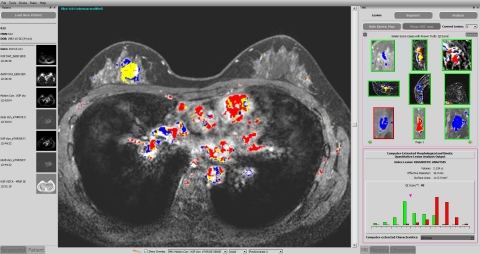

Qlarity Imaging’s software is used to assist radiologists in the assessment and characterization of breast lesions. Imaging features are synthesized by an artificial intelligence algorithm into a single value, the QI score, which is analyzed relative to a database of reference abnormalities with known ground truth. (Photo: Business Wire)

Qlarity Imaging’s software is used to assist radiologists in the assessment and characterization of breast lesions. Imaging features are synthesized by an artificial intelligence algorithm into a single value, the QI score, which is analyzed relative to a database of reference abnormalities with known ground truth. (Photo: Business Wire)